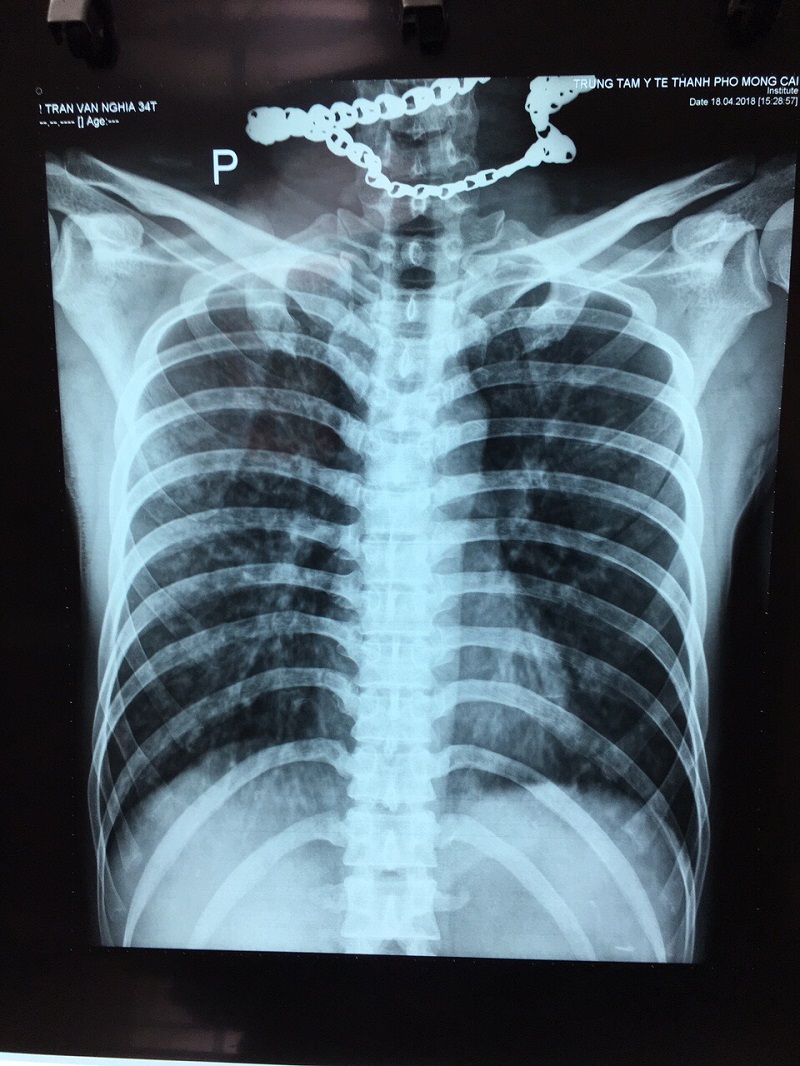

Sau 2 ngày điều trị người bệnh ổn định, đã tự đi lại, ăn uống bình thường.

Hình ảnh người bệnh: